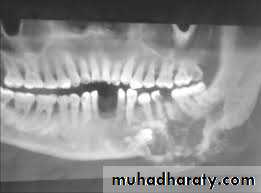

Multilocular radioluscency honey comb or soap bubble appearance.-In unicystic ameloblastoma unilocular radioluscency.

Thinning and expansion of cortical plate. Thinning of lamina dura.

Truncation /Amputation of roots